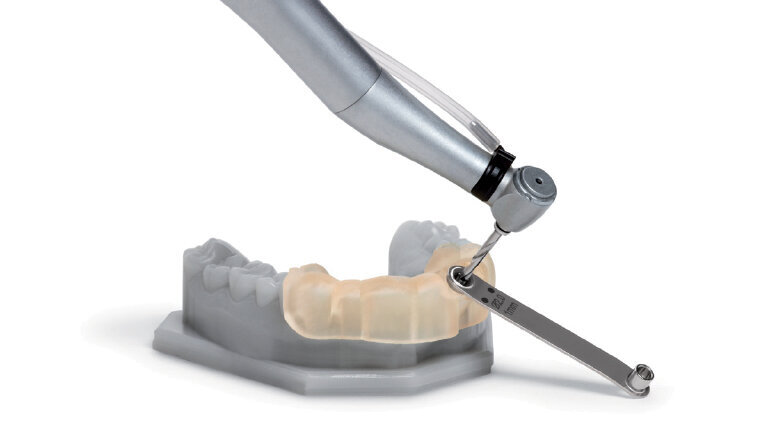

Obr. 1: CAD/CAM chirurgické šablony zcela omezují sklon vrtáku a hloubku preparace a jsou navrženy na základě dat týkajících se konkrétního pacienta z CBCT skenu a z intraorální kamery zpracovaných softwarem pro plánování implantátů